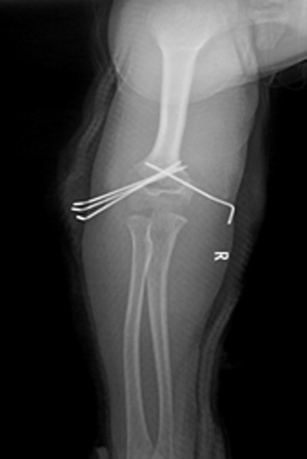

患儿,李XX,男性,12岁,主因“摔伤右肘疼痛、畸形、活动受限1天余”门诊入院。小儿肱骨髁上骨折根据Gartland分类法,分为I型无移位;II型有移位但后侧皮质完整;III型有移位且无骨皮质接触。此患者骨折分型为III型骨折,骨折移位通过外固定维持骨折位置困难,手术指征明确。入院后积极术前准备,于2018年6月5日行手术治疗,术中给予外侧三枚克氏针、内侧一枚克氏针固定,见骨折位置满意,术后石膏固定。

小儿肱骨髁上骨折复位不良产生的问题已受到广泛关注,以往肘内翻、肘外翻常常被认为是肱骨远端骺板早闭所致,但精准的解剖复位亦是预防以上并发症的重要因素。目前国内、国际的治疗方案为闭合复位克氏针内固定术,以往我区此类骨折患者均于北京上级医院就诊。此手术的成功完成,避免了患儿往返北京的奔波,同时进一步推动了我院小儿骨科的发展。

2.jpg术后